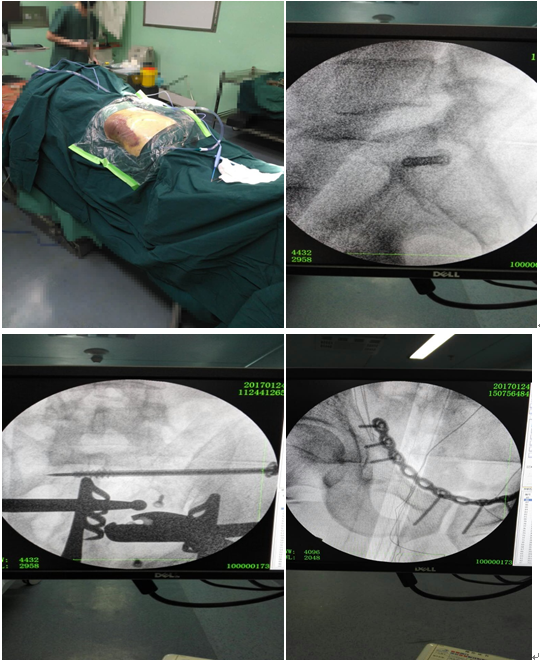

入院诊断:1、双侧耻骨上下支骨折;2、双侧坐骨支骨折;3、左骶骨骨折;4、左侧胫腓骨中下段开放性骨折;5、腰5椎体右侧横突骨折。刘利主任医师查看患者,阅片后指示:患者直接暴力损伤致骨盆前环损伤,左侧骶骨呈新月形骨折,伴有左侧坐骨神经损伤,左胫腓骨中下段呈开放性螺旋形骨折,需行手术治疗。入院当晚即行左胫骨中下段开放性骨折切开复位+外固定架固定术。术后切口无感染。左下肢行骨牵引,待患者病情平稳后于伤后第8天行双侧耻骨上支及左骶骨骨折切开复位内固定术,手术方法引用了当今流行的骶骨后路切开复位,C臂透视下闭合打入骶髂关节拉力螺钉固定骶骨骨折;以及改良Stoppa手术入路治疗骨盆前环损伤。手术进行顺利,病人病情平稳。

众所周知,骨盆骨折属于创伤骨科最为重要的部分之一,高能量骨盆损伤往往需要手术治疗,以挽救生命、防止骨盆不稳定或骨盆机型并发症的发生,其损伤大、死亡率高,复位困难等一直都是骨科医生棘手的问题。该患者如此高能量损伤实属罕见,在精心的术前准备及多次科内开展术前讨论的前提下,制定了该手术方案,优点:1、应用改良Stoppa手术入路不需切断腹直肌就可以有充分的手术视野去复位骨折。往往传统的手术入路在切断腹直肌后,术后患者会出现疼痛、切口下空虚,间隙形成,并有渗出,甚至感染;2、对两侧“死亡冠”区进行充分显露,结扎,避免术中及术后出血,危及生命,甚至死亡;3、利用后路小切口解决骶骨骨折的复位,并在透视下闭合打入骶髂关节拉力螺钉,减少了创伤出血,并达到了满意的稳定效果;4、一期行左胫骨开发性骨折切开复位外固定架固定术,顺应了当前应对开放性骨折的处理原则,不但减少了术后感染的风险,且同样有稳定效果;5、手术费用合理,减轻了患者的经济负担。该项技术填补我地区创伤骨科对骶髂关节螺钉固定技术及改良Stoppa手术入路治疗骨盆前环损伤的空白。?